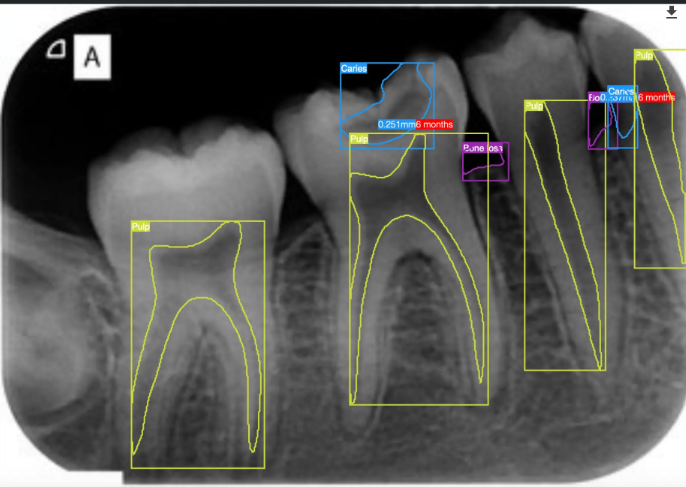

- Case Study 2: AI-assisted image analysis was used to detect early-stage caries in a 30-year-old patient, enabling minimally invasive treatment that preserved tooth structure.

- AI-assisted diagnostic tools have shown a 30% increase in the early detection of caries and periodontal diseases (Journal of Clinical Dentistry, 2023).

- Patient A: “Thanks to AI-assisted imaging, my dentist detected a cavity that would have otherwise gone unnoticed. The early intervention saved me from a more invasive procedure later on.”